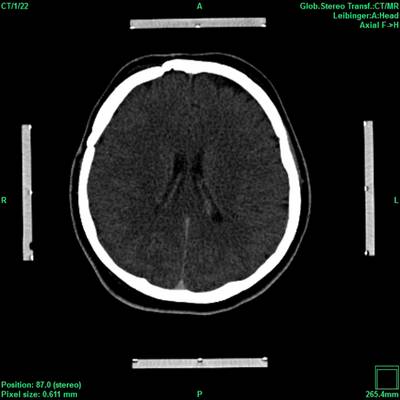

Moderne bildgebende Verfahren in Kombination mit den Entwicklungen im Bereich der elektronischen Datenverarbeitung verhalfen der stereotaktischen und funktionellen Neurochirurgie zum Durchbruch. Denn erst sie ermöglichten präzise und gewebeschonende Eingriffe wie zum Beispiel die Tiefe Hirnstimulation (THS) am menschlichen Gehirn.

Die hohe Qualität der Bilddarstellung zeichnet das inomed Planning System (iPS) aus. Die automatische Zusammenführung verschiedener Bildmodalitäten ermöglicht eine schnelle und sichere Verifikation der geplanten Zugänge. Diese Zugänge sind für eine erfolgreiche THS zwingend notwendig. Auf Wunsch lassen sich anatomische Atlanten über patientenbezogene Daten projizieren. Dies erlaubt wiederum die Verifikation anhand anatomischer Grundlagen.

Ein leistungsstarker mehrstufiger Fusions-Algorithmus ermöglicht das Zusammenführen digitaler Bildinformationen, wobei immer der Erhalt der exakten Patienten-Geometrie im Vordergrund steht, bei gleichzeitiger Optimierung von anatomischer Sichtbarkeit und Bildqualität. Dies bildet die Grundlage für sichere Hochrisiko-Eingriffe wie der THS oder stereotaktisch geführter Biopsien.